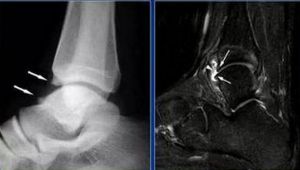

X線片顯示脛骨前唇和距骨骨質增生,MRI顯示距骨軟骨損傷,踝關節腔內積液。踝關節檢查時脛骨前緣或前內側有固定壓痛,背伸活動均不同程度受限,部分踝關節僵硬。